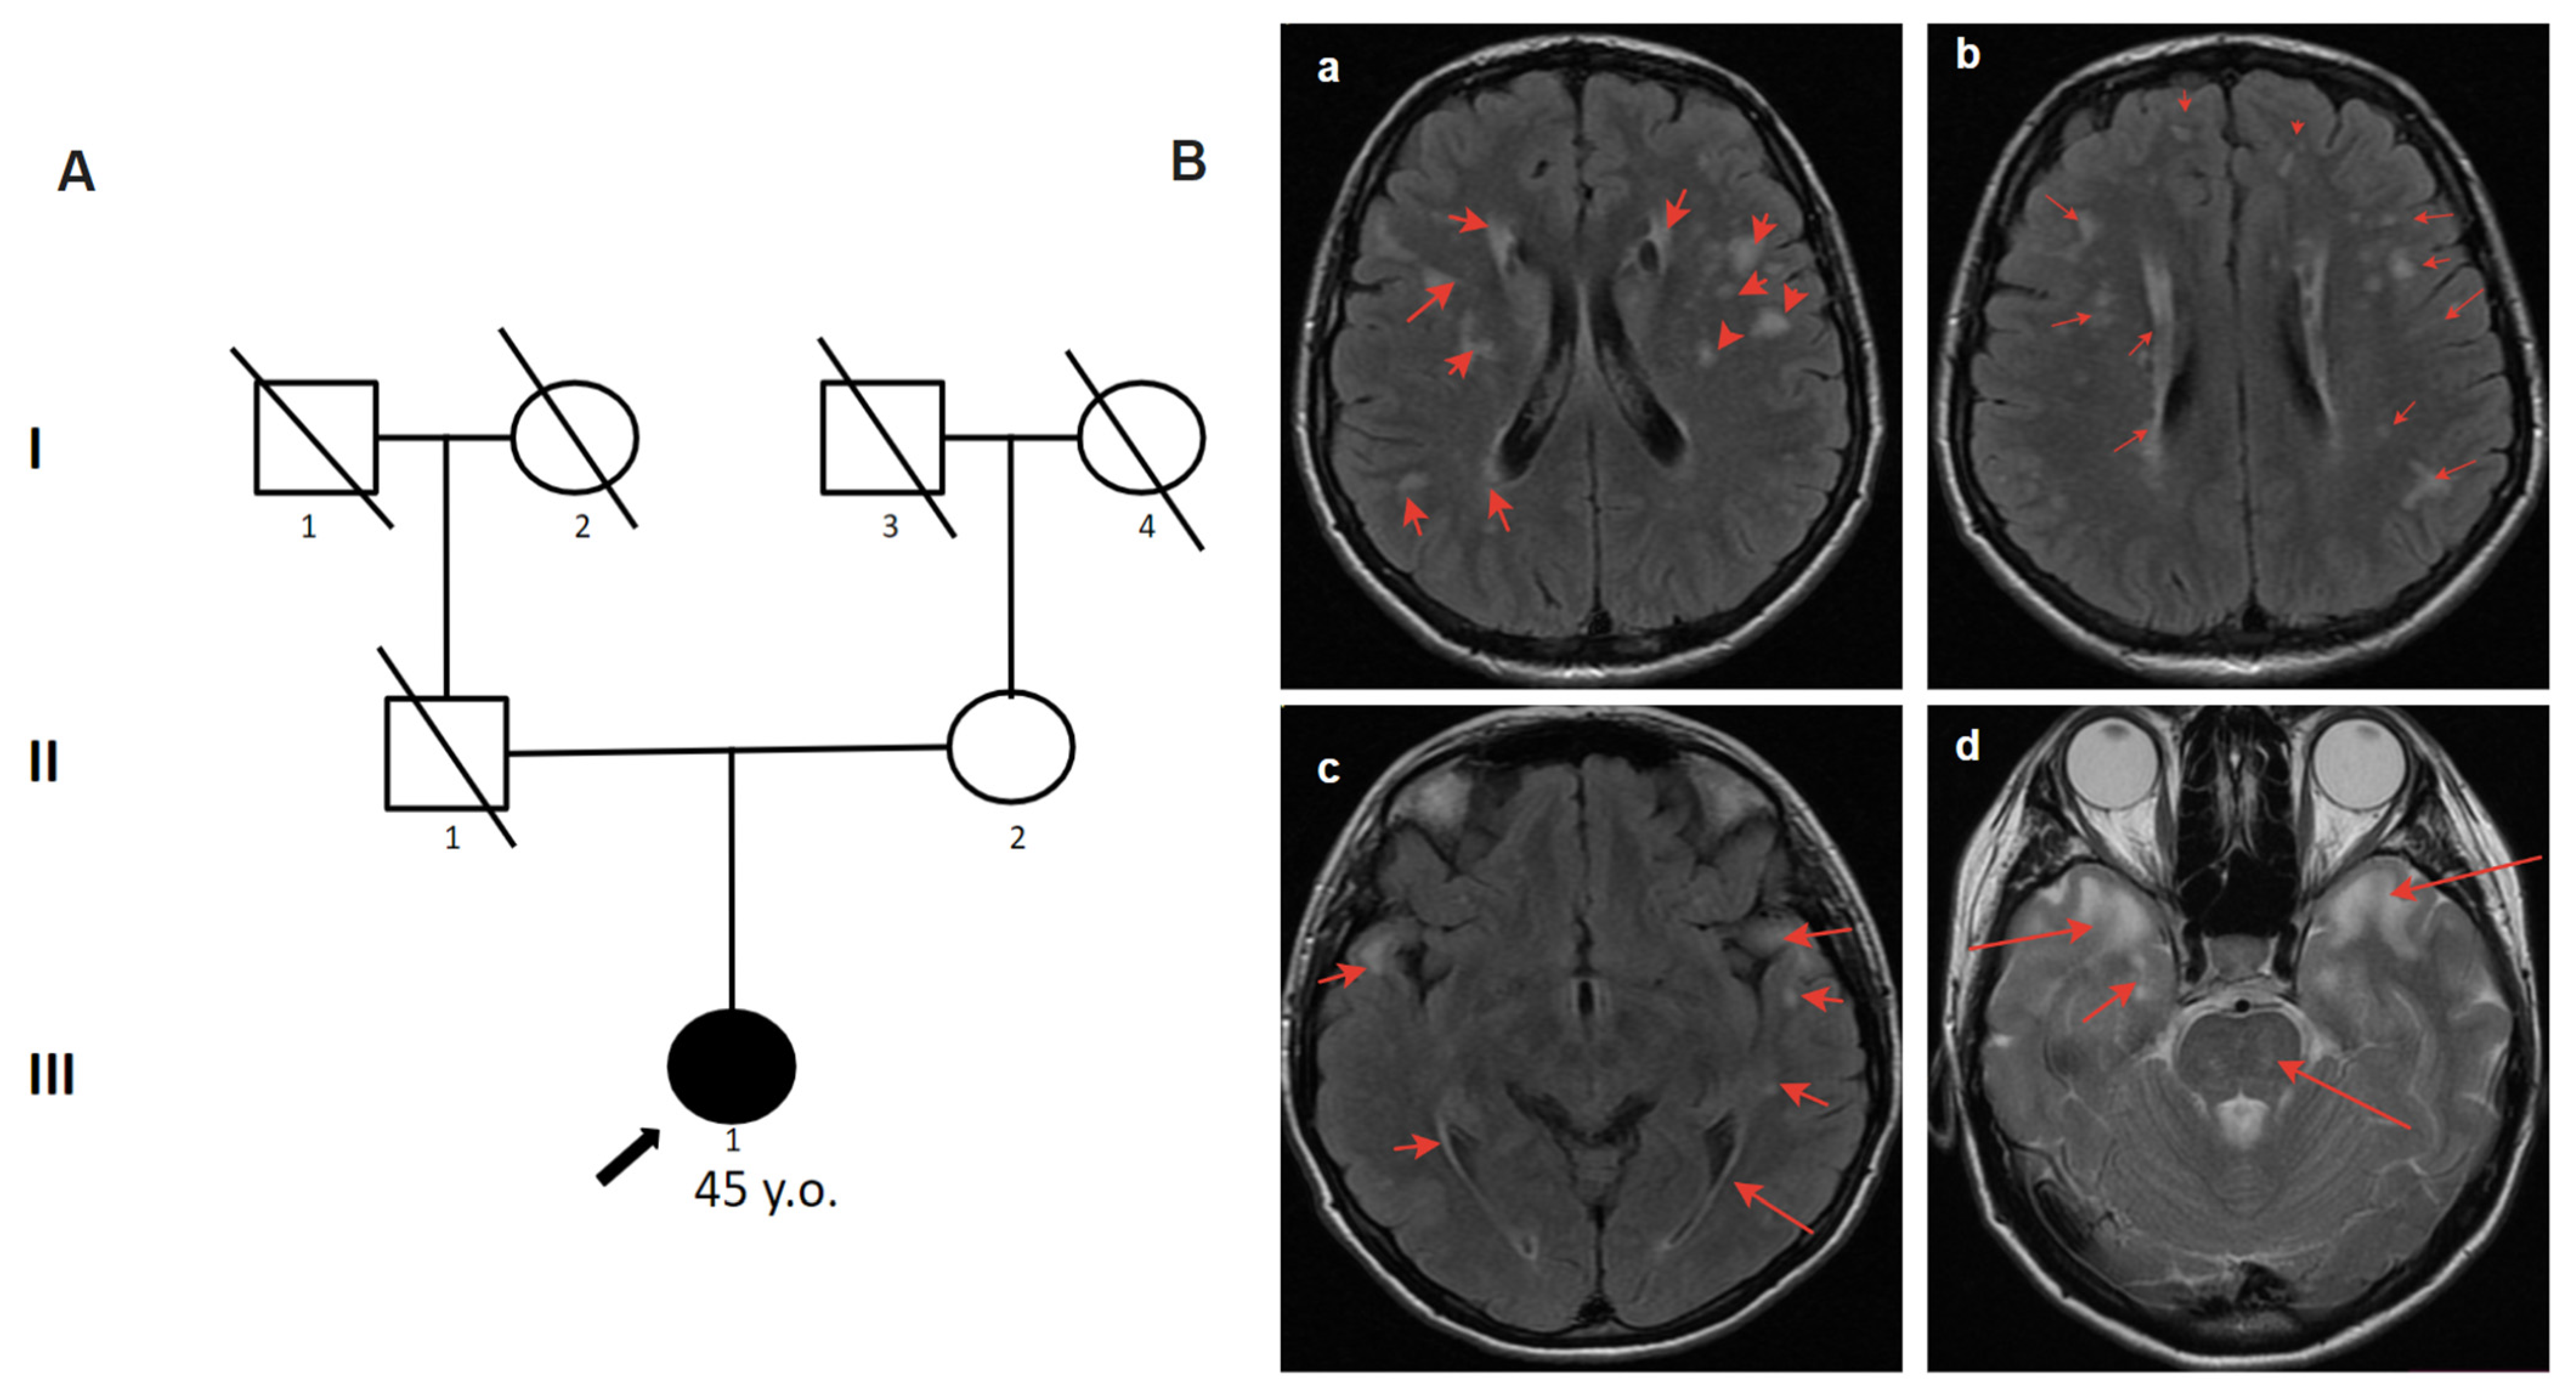

2.4.2. Patient 2